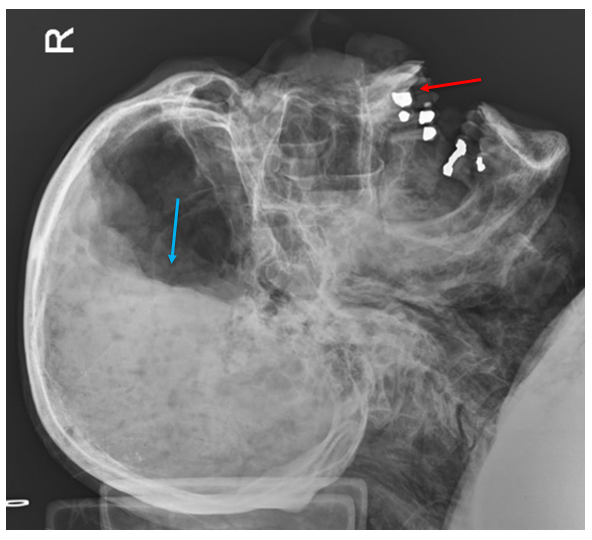

The second pathway by which we reach an undetermined manner is when extensive decomposition or other soft tissue loss (such as fire damage) interferes with our ability to determine a cause of death. Think of completely skeletal remains discovered in an abandoned building. Sometimes, indicators of potentially lethal injuries can still be identified – for example, a gunshot wound of the skull or knife marks on a rib. But, as the aphorism goes, “an absence of evidence isn’t necessarily evidence of absence” – a bullet or blade could be lethal while only striking soft tissue (especially in regions like the abdomen or neck). If we cannot rule out non-natural causes of death, the best choice for manner is “undetermined.”